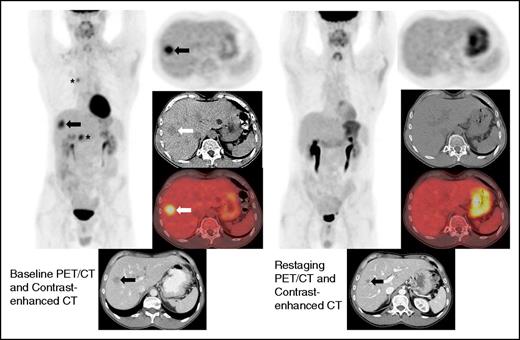

This case illustrates a discrepancy between the revised Lugano Classification (PD) and the immune-related response criteria (PR) given the fact that the immune-related response criteria do not take into consideration PET/CT findings. This type of discrepancy is particularly notable in cases with bone marrow involvement. Oftentimes, lymphomatous involvement of the bone marrow is either not measurable (due to absence of soft tissue component) or imperceptible on CT. Therefore, these findings cannot be integrated in the tumor burden of the immune-related response criteria. Restaging PET-CT is at 12 weeks. Restaging PET/CT 2 at 20 weeks demonstrates new areas of FDG uptake in the left side of T9 vertebral body (arrows) and increasing uptake in the left acetabulum, suggesting increasing extent of marrow disease, whereas this is barely seen on CT. Marked physiologic uptake is also seen in brown fat (asterisks).